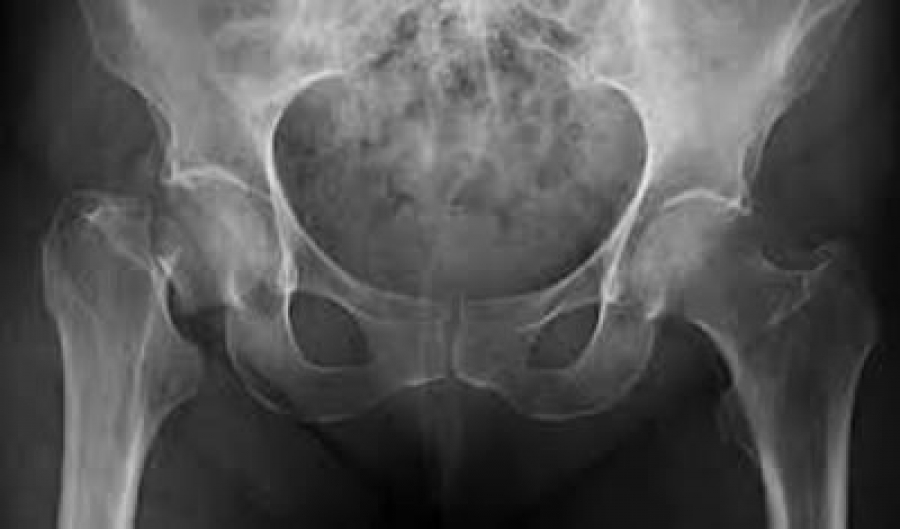

La osteoporosis es una enfermedad crónica y progresiva que afecta a los huesos, como consecuencia los huesos se vuelven frágiles y pueden llegar a producirse fracturas por caídas simples o realizando actividades que requieren de un esfuerzo mínimo.

En México, las fracturas más comunes son la de muñeca, cadera, columna y húmero. Estudios afirman que las personas que han tenido una fractura a causa de la osteoporosis aumentan en un 87%, la probabilidad de tener una segunda fractura en el futuro.